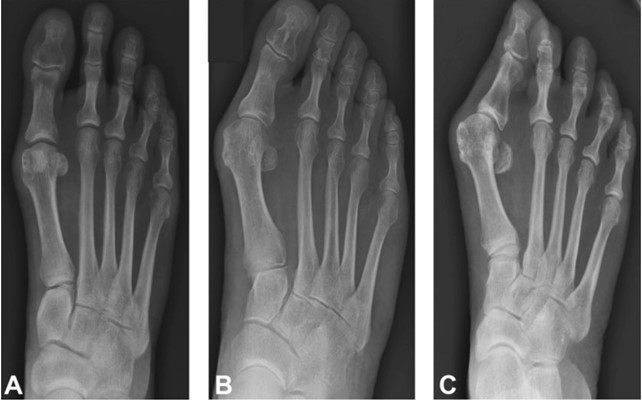

X ray of 3 feet, comparing bunions

A physician will diagnosis a bunion based on the patient’s history, physical examination and radiographs. A thorough physical examination can help dictate the appropriate treatment options available for the patient. Severity of the deformity can be determined with the help of X-rays. Bunions can be classified by severity into three groups based on the measurements of the hallux valgus angle (HVA) and the first-second intermetatarsal angle (IMA). The hallux valgus angle is defined as the angle between the big toe and the first metatarsal. The intermetatarsal angle is the angle of the long axis of the first and second metatarsals4.